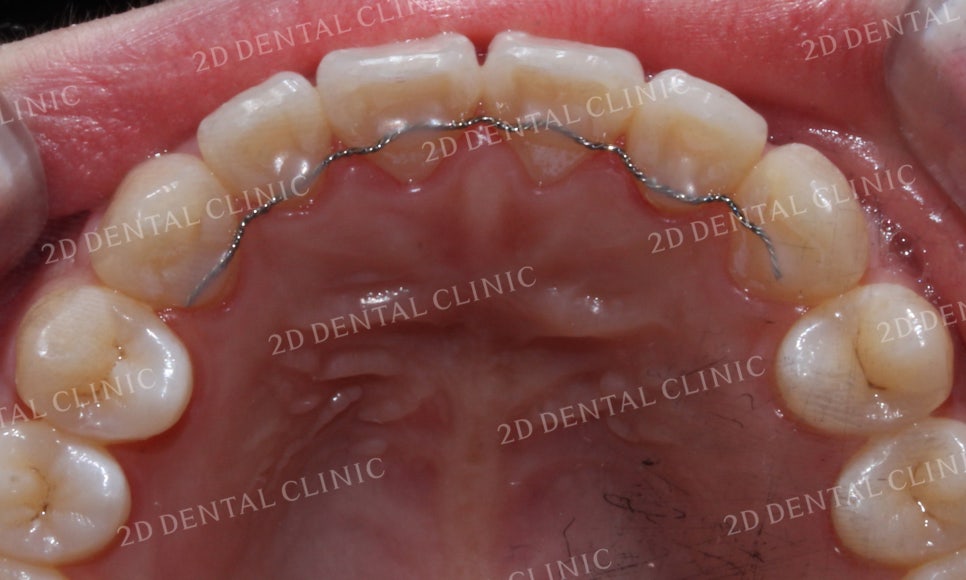

상악의 설측면 사진을 보시면

전치부 치열이 미세하게

들쭉날쭉한 모습이네요.

상악 설측면의 모습을 보면

교정 전후 삐뚤거리던 전치부 치열이

가지런하게 배열된 모습을 볼 수 있습니다.

또한 눈에 띄게 튀어나와 있던

중절치가 돌출감 없이 잘 마무리된 모습이네요!